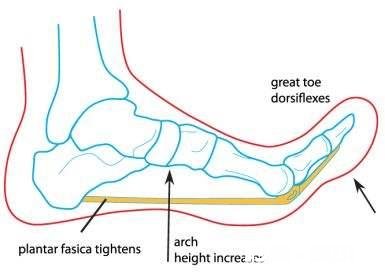

足底筋膜,在我们的脚底,从跟骨往前延伸到脚趾下,把我们的脚趾都往上翘,能摸到脚底变硬了,那就是我们的足底筋膜 。当我们的脚趾往上翘的时候,附着在跟骨下方的肌腱是被往前拉的,时间久了,骨刺就被拉出来了!这才是足底骨刺的最大原因!

足底筋膜从后跟往前延伸到脚趾下方 。

跟骨的骨刺大多数都不是垂直向下的,而是往前的 。所以骨刺怎么会扎到肉里呢?